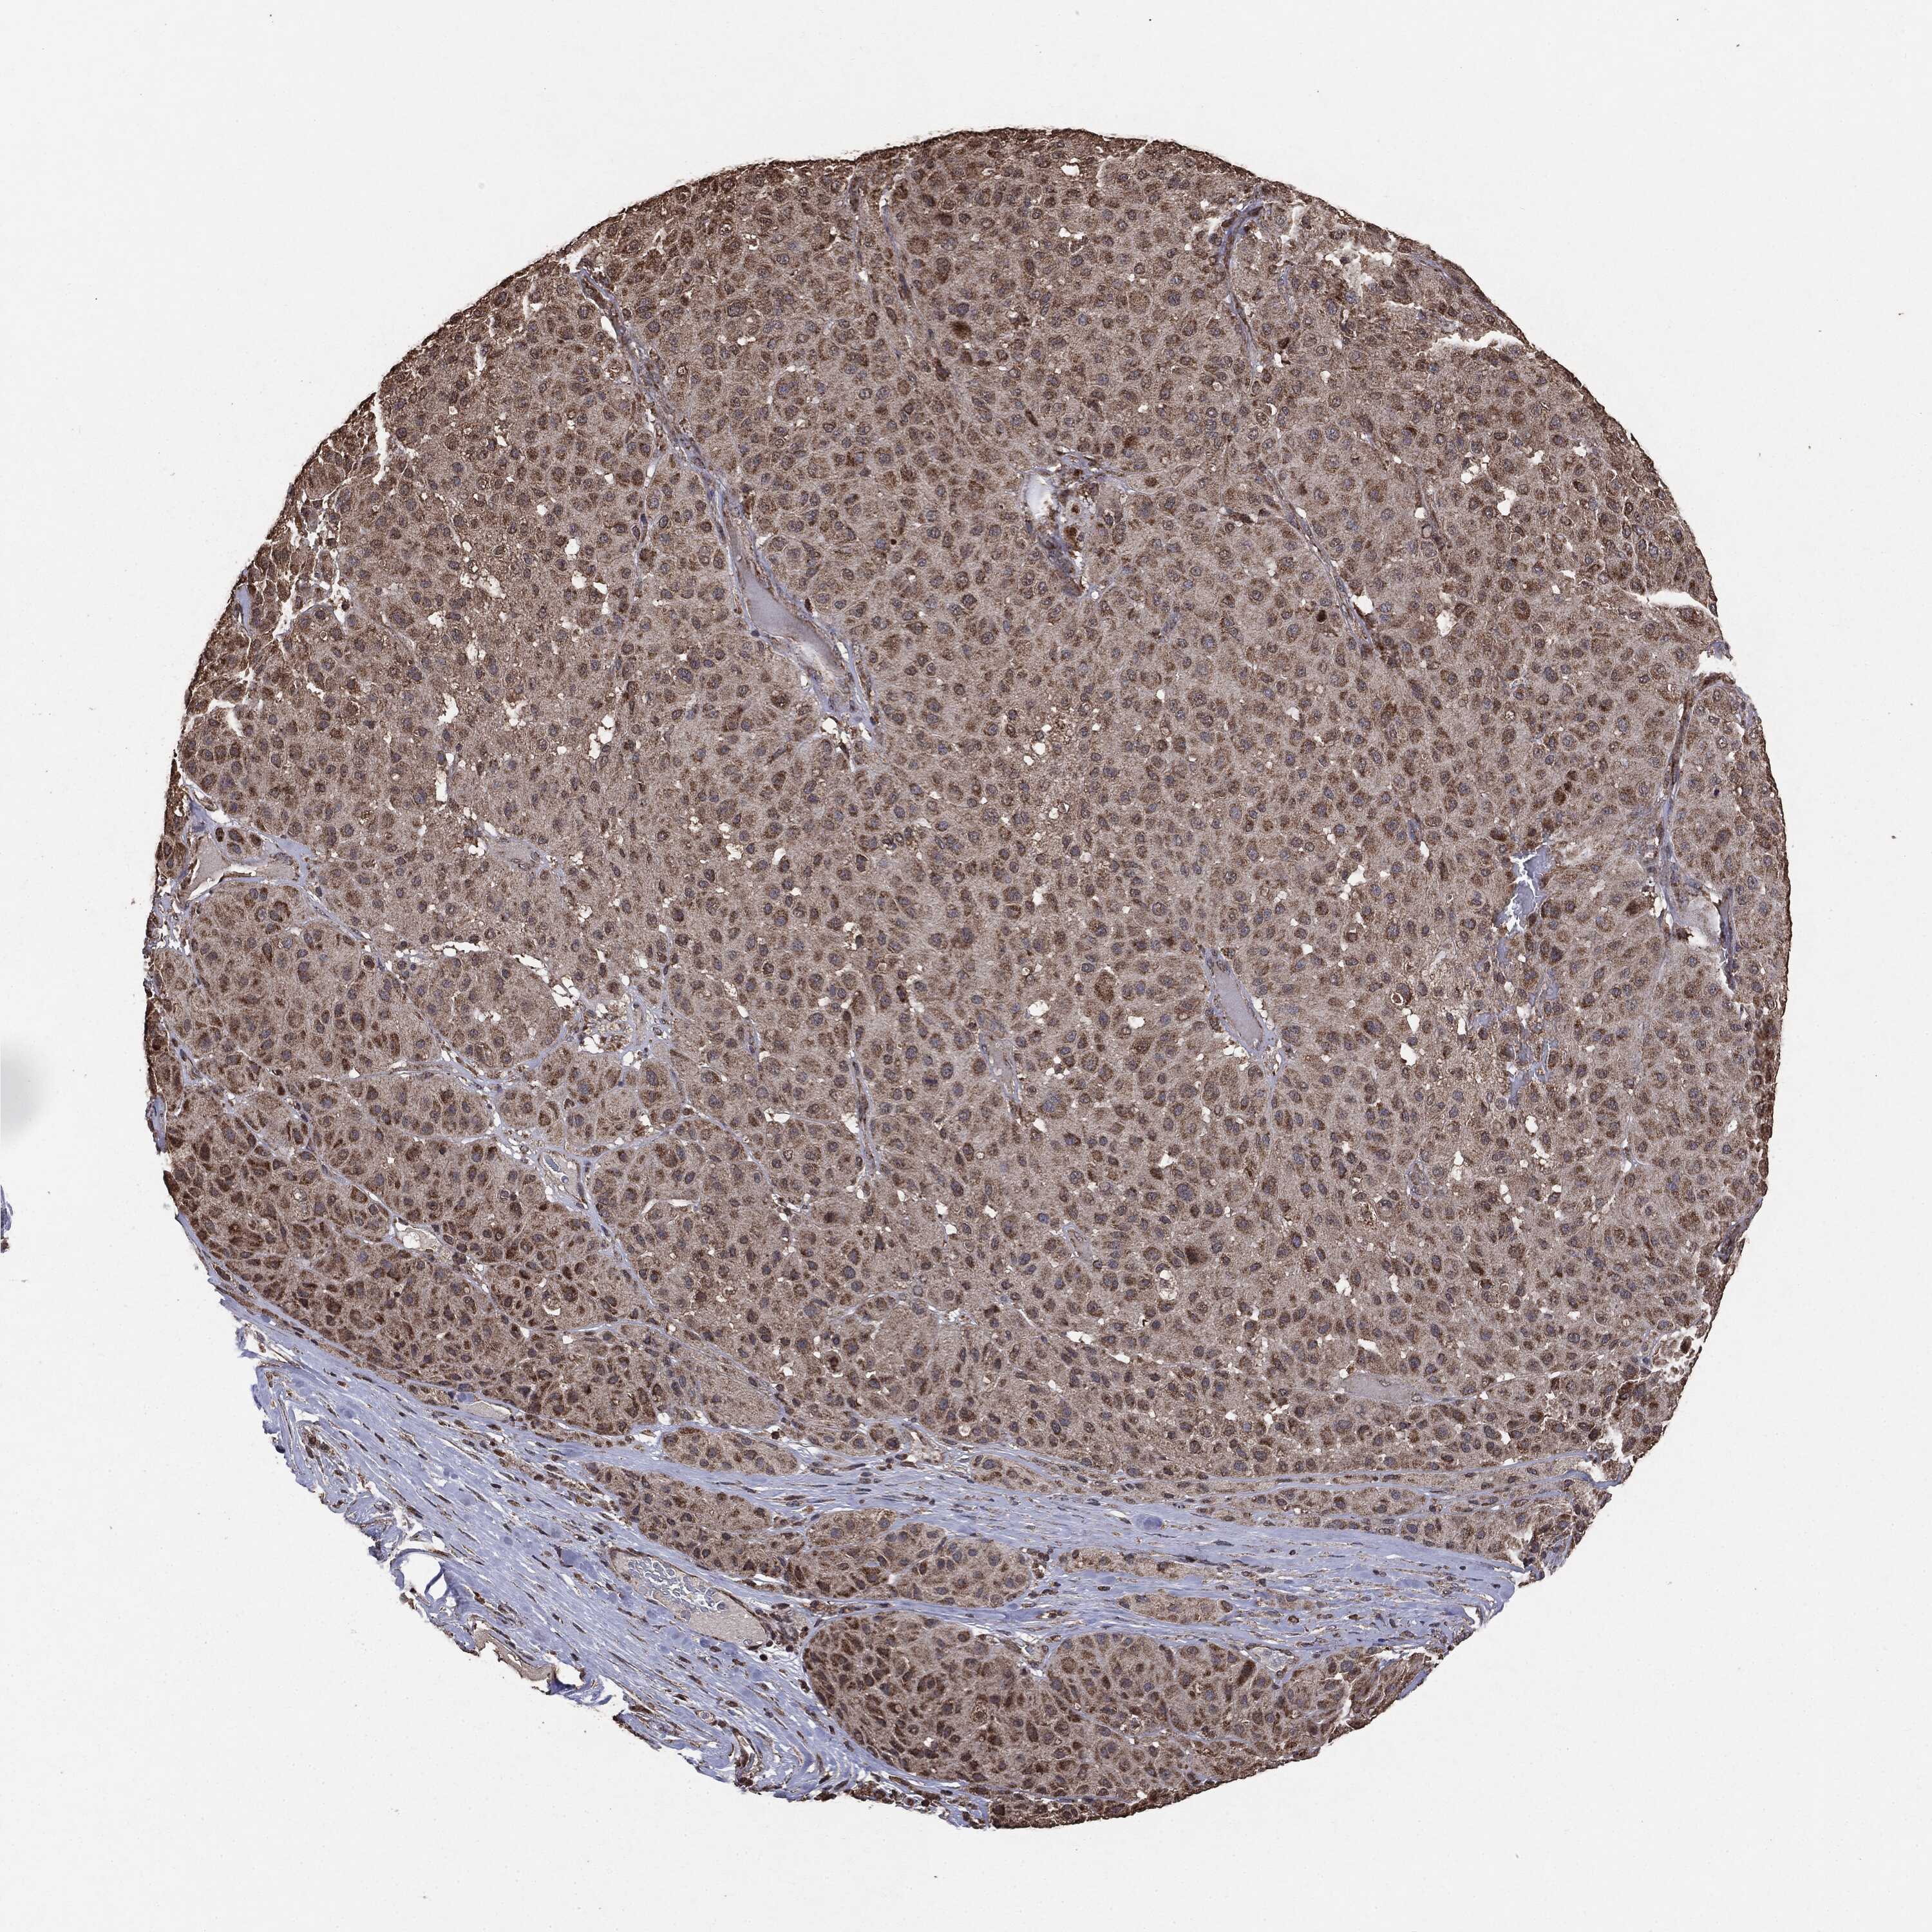

MELANOMA - Protein expressioni

A mouse-over function shows sample information and annotation data. Click on an image to view it in a full screen mode. Samples can be filtered based on level of antibody staining by selecting one or several of the following categories: high, medium, low and not detected. The assay and annotation is described here.

Note that samples used for immunohistochemistry by the Human Protein Atlas do not correspond to samples in the TCGA dataset.

Antibody stainingi

Antibody staining in the annotated cell types in the current human tissue is reported as not detected, low, medium, or high, based on conventional immunohistochemistry profiling in selected tissues. This score is based on the combination of the staining intensity and fraction of stained cells.

Each image is clickable and will lead to virtual microscopy that enables deeper exploration of all samples and also displays staining intensity scores, fraction scores and subcellular localization as well as patient and tissue information for each sample.

CAB069425

CAB080053

CAB080065

CAB080070

CAB080081

CAB080095

CAB080097

Staining

High

Medium

Low

Not detected

Intensity

Strong

Moderate

Weak

Negative

Quantity

>75%

75%-25%

<25%

None

Location

Nuclear

Cytoplasmic/membranous

Cytoplasmic/membranous,nuclear

Malignant melanoma, NOS

Malignant melanoma, Metastatic site